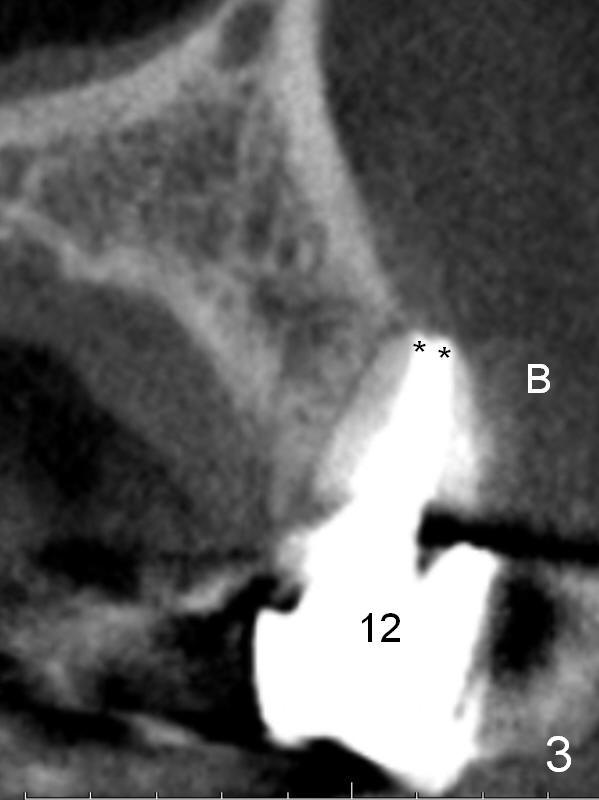

A 57-year-old lady had poor dentition, including periapical radiolucency of the tooth #12, 8 years ago (Fig.1 *, 2007). After comprehensive treatment, the pathology is apparently under control (Fig.2 <, 2011). CBCT shows the pathology not completely resolved (Fig.3,4, coronal section, 2012). Early this year, there was sign of crack tooth at #12 (Fig.5 arrowheads). Last Saturday she returned because of dislodgement of the crown and post. The tooth is found to be non salvageable.

After extraction, the bottom of the socket must be oblique (Fig.9 arrowheads). As usual, osteotomy is initially at the junction of palatal (Fig.10 P) 1/3 and middle 1/3 perpendicular to the plate. Once the drill gets engaged, the trajectory is to be changed (Fig.11 curved arrow) so that the apical end of the osteotomy (red line) is as close to the buccal plate (B) as possible. The purpose is to keep the palatal end of the osteotomy as palatal as possible. In spite of the effort, an angled abutment is expected, as large as 20 degree (Fig.8 purple angle).